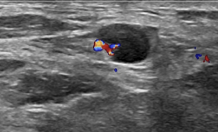

• *Enlarged nodes**

• Normal morphology

Increased vascularity

• *Matted mass**

• Fused nodes

• *Abscess formation**

• *-** Heterogeneous mass

• Thick irregular walls

• Increased peripheral vascularity